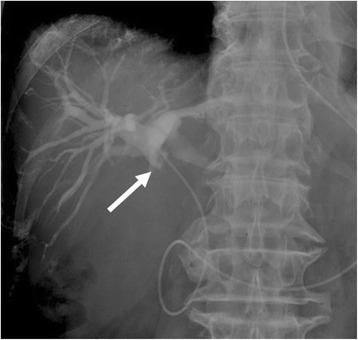

Endoscopic retrograde cholangiopancreatography (ERCP) demonstrated severe intrahepatic bile duct dilatation and a filling defect in the mid-CBD. The tumor was involved with the cystic duct. After the ERCP, endoscopic placement of a nasobiliary biliary drainage catheter was performed (Fig. 2). The bile and brush cytology performed at the same time revealed a few degenerative atypical cells (class 3).